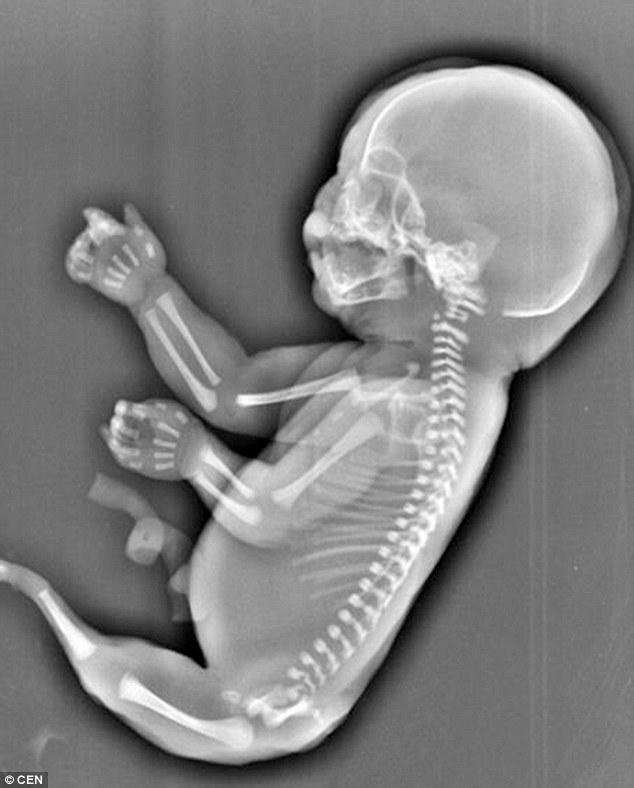

Ảnh scan cho thấy người mẹ trẻ ở Trung Quốc mang một thai nhi giống "nàng tiên cá"

Các bác sĩ tại bệnh viện nói với Wu rằng thai nhi mắc phải Hội chứng Người cá, một dạng dị tật bẩm sinh rất hiếm gặp khiến hai chân hợp nhất với nhau, hình thành một cái đuôi giống như đuôi của nàng tiên cá. Theo các chuyên gia, nhiều khả năng thai nhi chỉ có thể tồn tại trong một vài giờ sau khi sinh. Wu đã buộc phải quyết định bỏ đứa bé dù thai nhi đã được 6 tháng tuổi.

Nguyên nhân của hội chứng Người cá đến nay vẫn là một bí ẩn y học. Hiện tượng này chỉ xảy ra với xác suất 1 trên 100.000.